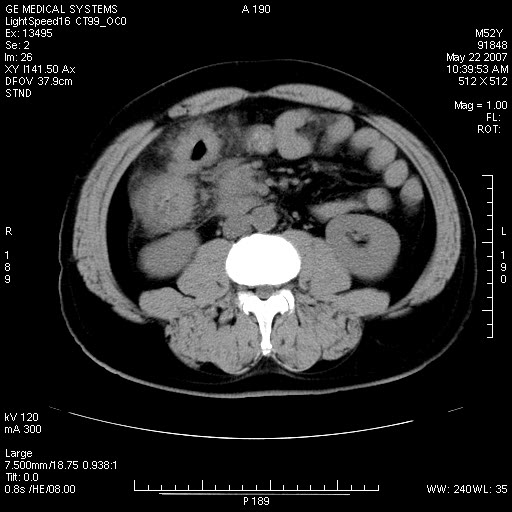

以下是引用余辉在2007-5-22 20:12:00的发言:[br]升结肠管壁明显增厚,增强有静脉期持续增强,结合患者病史,考虑结肠癌可能性大,临近脂肪影密度增高,混浊,恐有肠系膜浸润转移,建议镜检

以下是引用dyqct在2007-5-22 20:43:00的发言:[br]支持结肠肝曲占位性病变(浸润型结肠癌可能性大)。胆总管下端扩张,原因待查。

以下是引用gaoxiao在2007-5-22 20:49:00的发言:[br]考虑升结肠癌向周围侵犯,胰头钩突受侵。